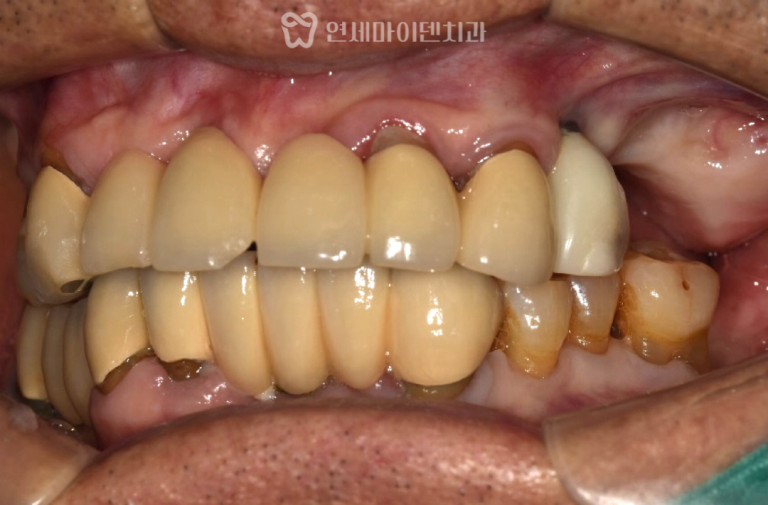

치료결과: 모든 영구치 보존, 배열 완료

약 32개월의 치아 교정 끝에

다음과 같은 결과를 얻었습니다.

- 모든 영구치 보존 성공

- 송곳니 포함 전체 치아 배열 정상화

- 앞니·어금니 교합 정리 완료

- 약간의 잇몸라인 비대칭 및 중심선 1mm 차이는 잔존

- 앞니 뿌리를 최대한 보존하면서 송곳니를 정상 맹출시킨 점이 큰 의의

이 케이스는 “송곳니를 발치하지 않고

살릴 수 있느냐”가 핵심이었던 만큼

정밀 진단과 협진의 중요성이

다시 한 번 확인된 치료였습니다.